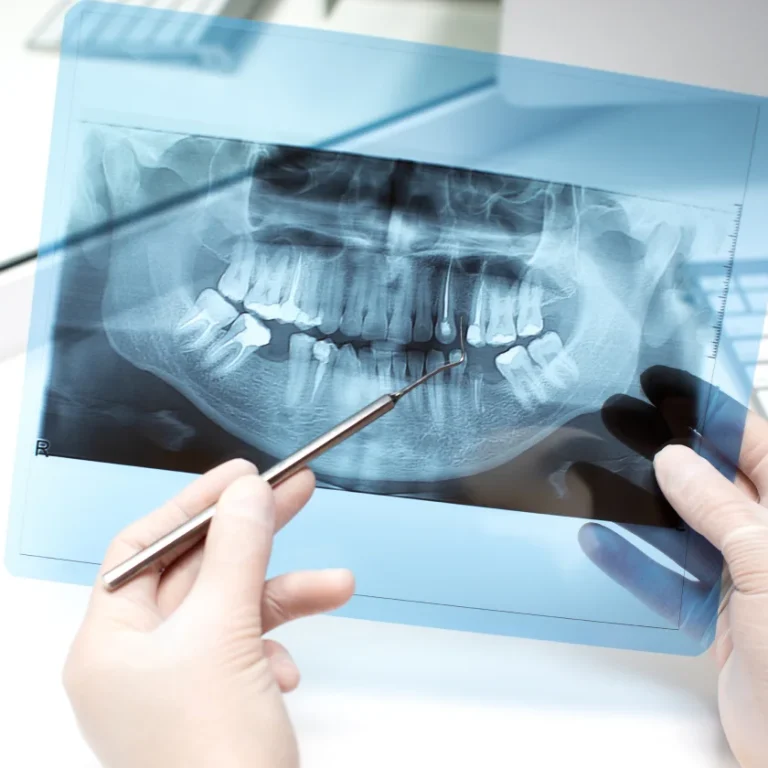

A chipped tooth can be the root of many other problems if left alone.